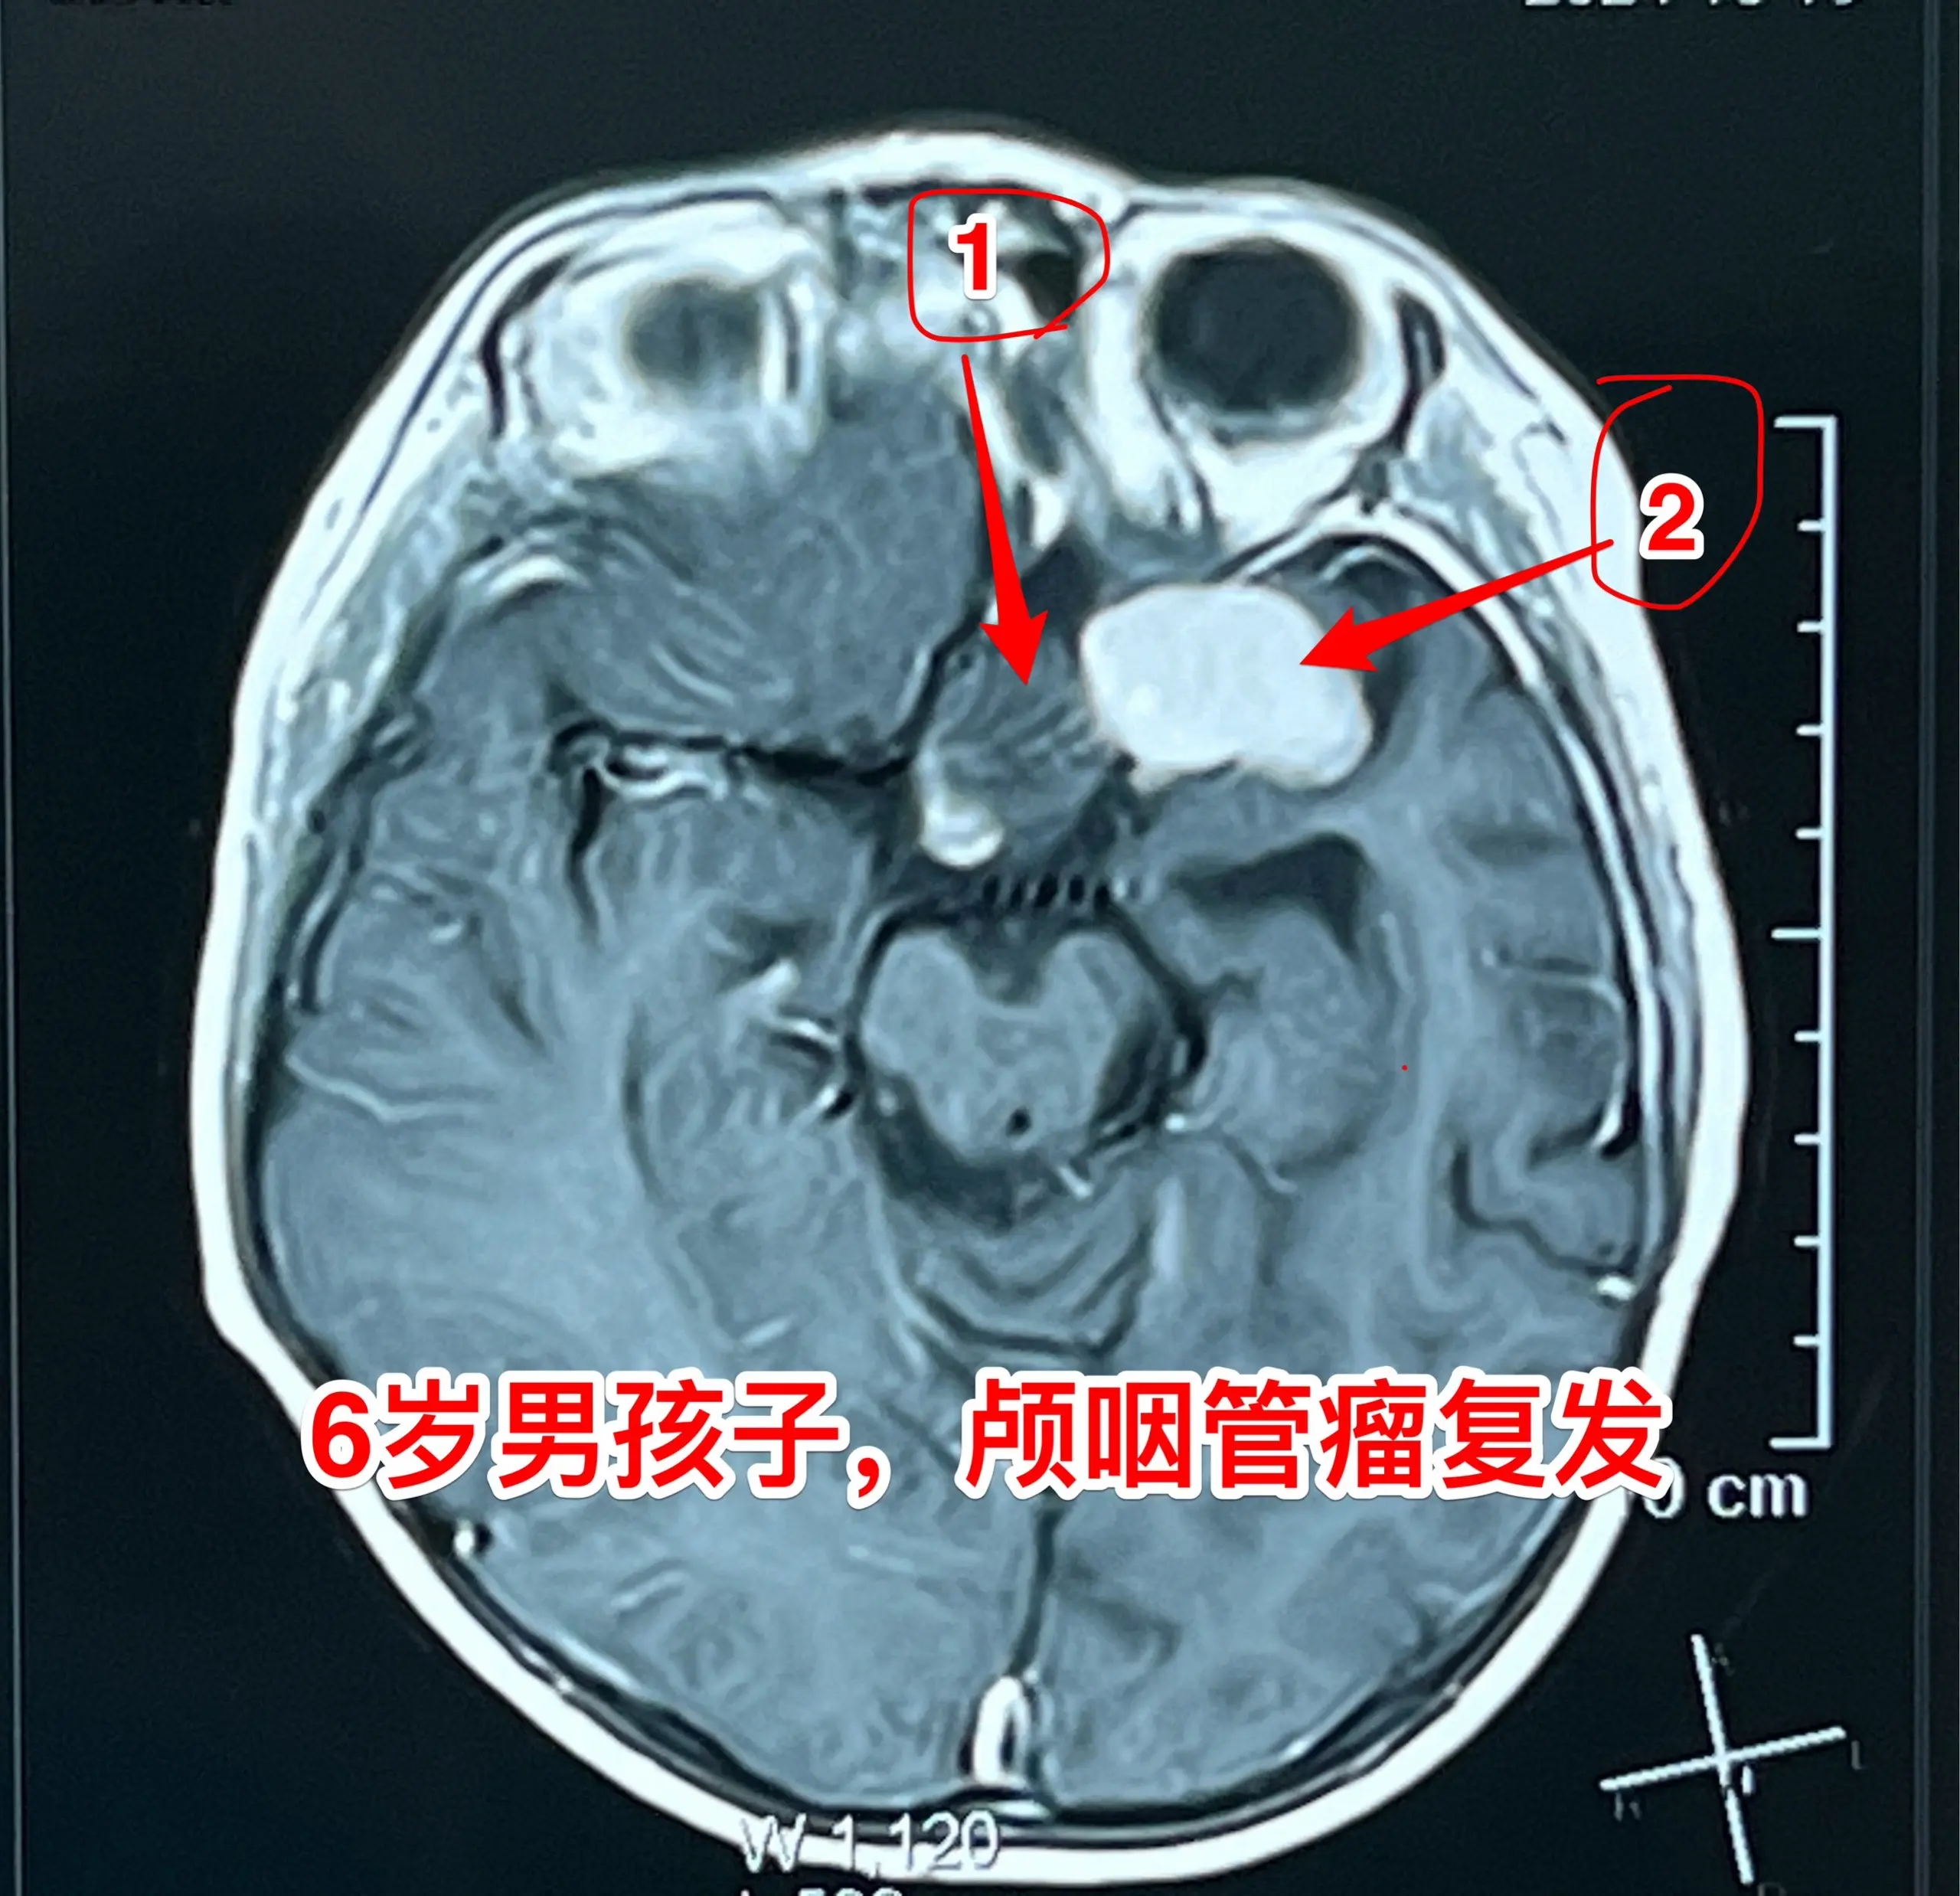

今日两个颅咽管瘤手术。1,6岁男孩子,安徽宿州人。2023年5月因视力下降发现了脑部长了巨大颅咽管瘤,见图1。家长曾经通过微信找我看过,最终选择在上海某医院行手术治疗,手术后出现右侧偏瘫,经过康复治疗后能勉强走路,但是右手还不能拿笔写字。2023.12磁共振就显示颅咽管瘤复发了(多块肿瘤复发)。2024.10又出现视力下降,故来找我作手术。今天手术中发现有四块较大的肿瘤,同时有很多个小钙化。所见肿瘤均顺利切除了。对比两次手术前的磁共振,可以说第一次手术更容易达到完全切除肿瘤,很遗憾,那一次机会错过了。 2,9岁男孩子,江苏盐城市的。因头痛、呕吐检查发现脑部有典型的颅咽管瘤,伴有脑积水。病人到我科住院后经用甘露醇和地塞米松后头痛、呕吐症状消失,能正常吃喝。今日作了开颅手术,顺利切除肿瘤。